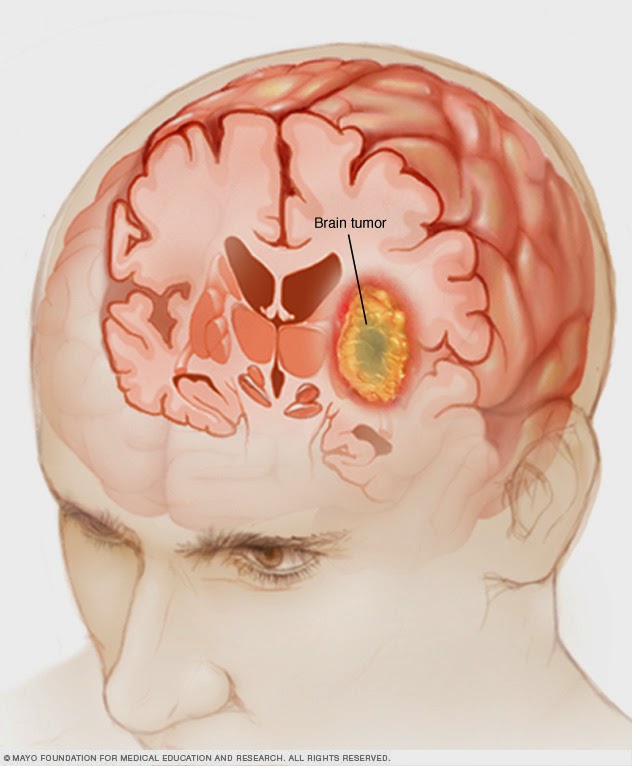

Tumor cerebral: condición que puede afectar funciones ... 😈

¿Cuántos tipos de tumores cerebrales hay? | Confirmado 😈

Tumor cerebral, ¿qué es y cuando ir al médico ... 😈